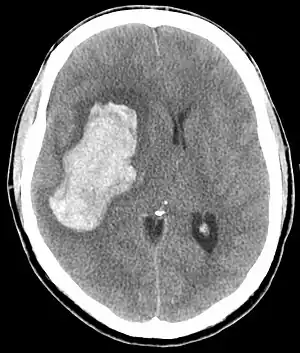

CT scan of an intracranial hemorrhage, a possible complication of hypertensive emergency.